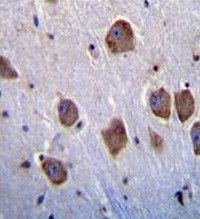

Supportive validation

- Submitted by

- antibodies-online (provider)

- Main image

- Experimental details

- IHC